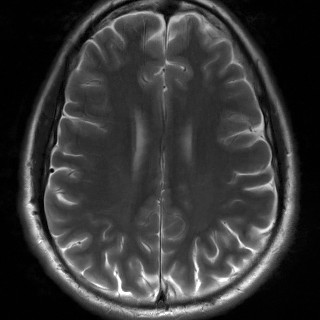

We consider the Cartesian multi-coil MRI problem. In this setup, and assuming coils, the signal measured by each coil writes as , where the are the sensitivity maps (or S-maps). We provide reconstruction metrics for the multi-coil setting in Table 2 and associated visuals in Figure 8. We provide comparisons with the baseline UNet from Zbontar et al. (2018). Both methods perform similarly up to the addition of mild residual noise with the UNet, yielding lower PSNR despite similar visual results. We stress that since PDNet contains learnable layers acting in the measurement domain, one would need to retrain the architecture for this new setting specifically, hence we do not present the results.

Multi-coil MRI

We provide in Figure 9 results on the multi-coil MRI inverse problem where we simulate coil maps. The UNet reconstruction shows a less smooth aspect, penalizing PSNR.

| Observed | UNet | RAM | Ground-truth |

![]() |

| (PSNR, SSIM) | (30.7, 0.860) | (35.5, 0.937) |